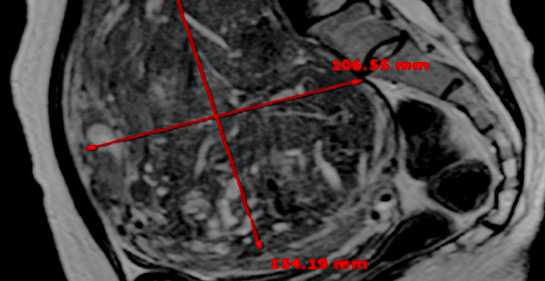

MRI촬영으로 자궁근종의 상태(위치, 개수, 크기, 모양 등), 자궁근종의 혈액공급 및 혈류,

자궁근종과 인접한 주요장기 및 구조, 초음파 발사경로의 확보 등을 분석함.

또한, 정밀초음파는 제거할 자궁근종의 개수, 자궁근종의 치료 슬라이스 수와

각 슬라이스의 체적, 근종제거마진, 근종과 인접한 장기와의 상관관계 등을 분석합니다.